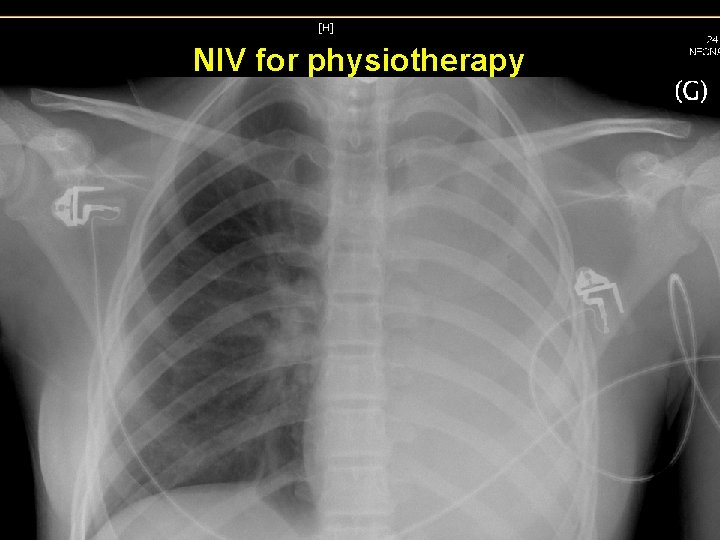

NIV for physiotherapy